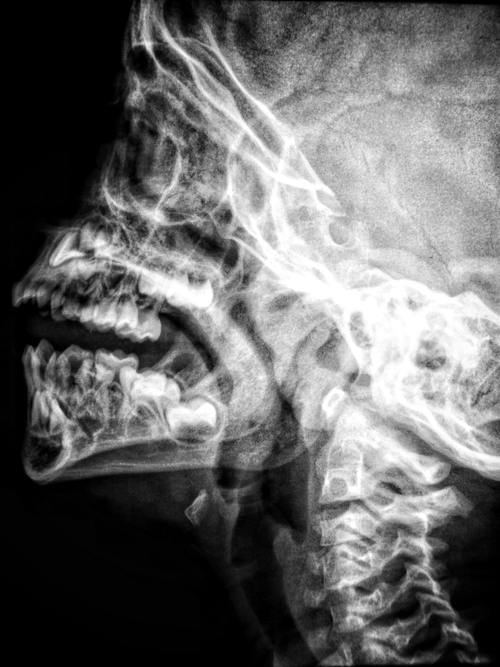

If water entered the larynx, the epiglottis’ natural response would be to close the airways to prevent aspiration. The larynx would reflexively trigger coughing to expel the fluid, or you would try to remove the fluid through exhalation. Even a small amount of fluid can induce laryngospasm, which will stimulate this powerful reflex.

This passage from Marieb and Hoehn’s Human Anatomy and Physiology is a good overview of how the epiglottis works: “When only air is flowing into the larynx, the inlet to the larynx is wide open and the free edge of the epiglottis projects upward. During swallowing, the larynx is pulled superiorly and the epiglottis tips to cover the laryngeal inlet. Because this action keeps food out of the lower respiratory passages, the epiglottis has been called the guardian of the airways. Anything other than air entering the larynx initiates the cough reflex to expel the substance.”